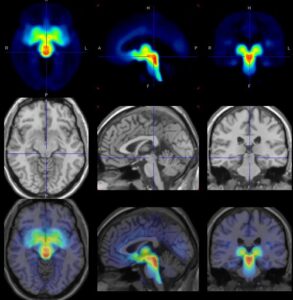

Mehr erfahren zu: "Depression vor den Tagen: Serotonin-Transport im Gehirn erhöht" Depression vor den Tagen: Serotonin-Transport im Gehirn erhöht